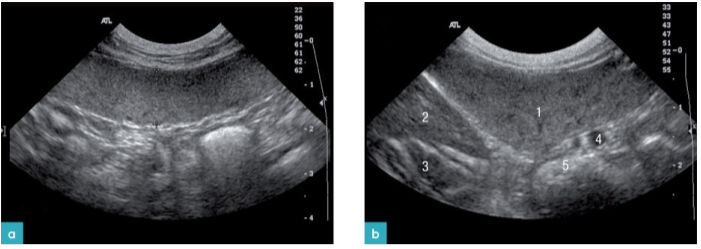

在41%的猫髓外造血病例中,伴有或不伴有淋巴样增生,脾脏肿大且回声正常(图12和13)。一部分病例可见,脾脏上有直径0.7-3cm不等的低回声结节或团块。另一些病例可见实质呈低回声,外观呈斑纹状。

组织胞浆菌病是猫的第二大常见的真菌疾病。是猫脾脏肿大鉴别诊断的疾病之一,脾脏实质呈现均匀低回声,有结节样或斑驳的外观。